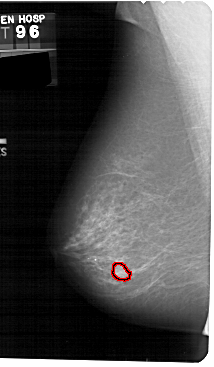

A_1534_1.LEFT_CC

LEFT_CC LINES 5401 PIXELS_PER_LINE 2881 BITS_PER_PIXEL 12 RESOLUTION 43.5 OVERLAY

FILE: A_1534_1.LEFT_CC.OVERLAY

TOTAL_ABNORMALITIES 1

ABNORMALITY 1

LESION_TYPE MASS SHAPE IRREGULAR MARGINS ILL_DEFINED

ASSESSMENT 4

SUBTLETY 4

PATHOLOGY MALIGNANT

TOTAL_OUTLINES 1

BOUNDARY